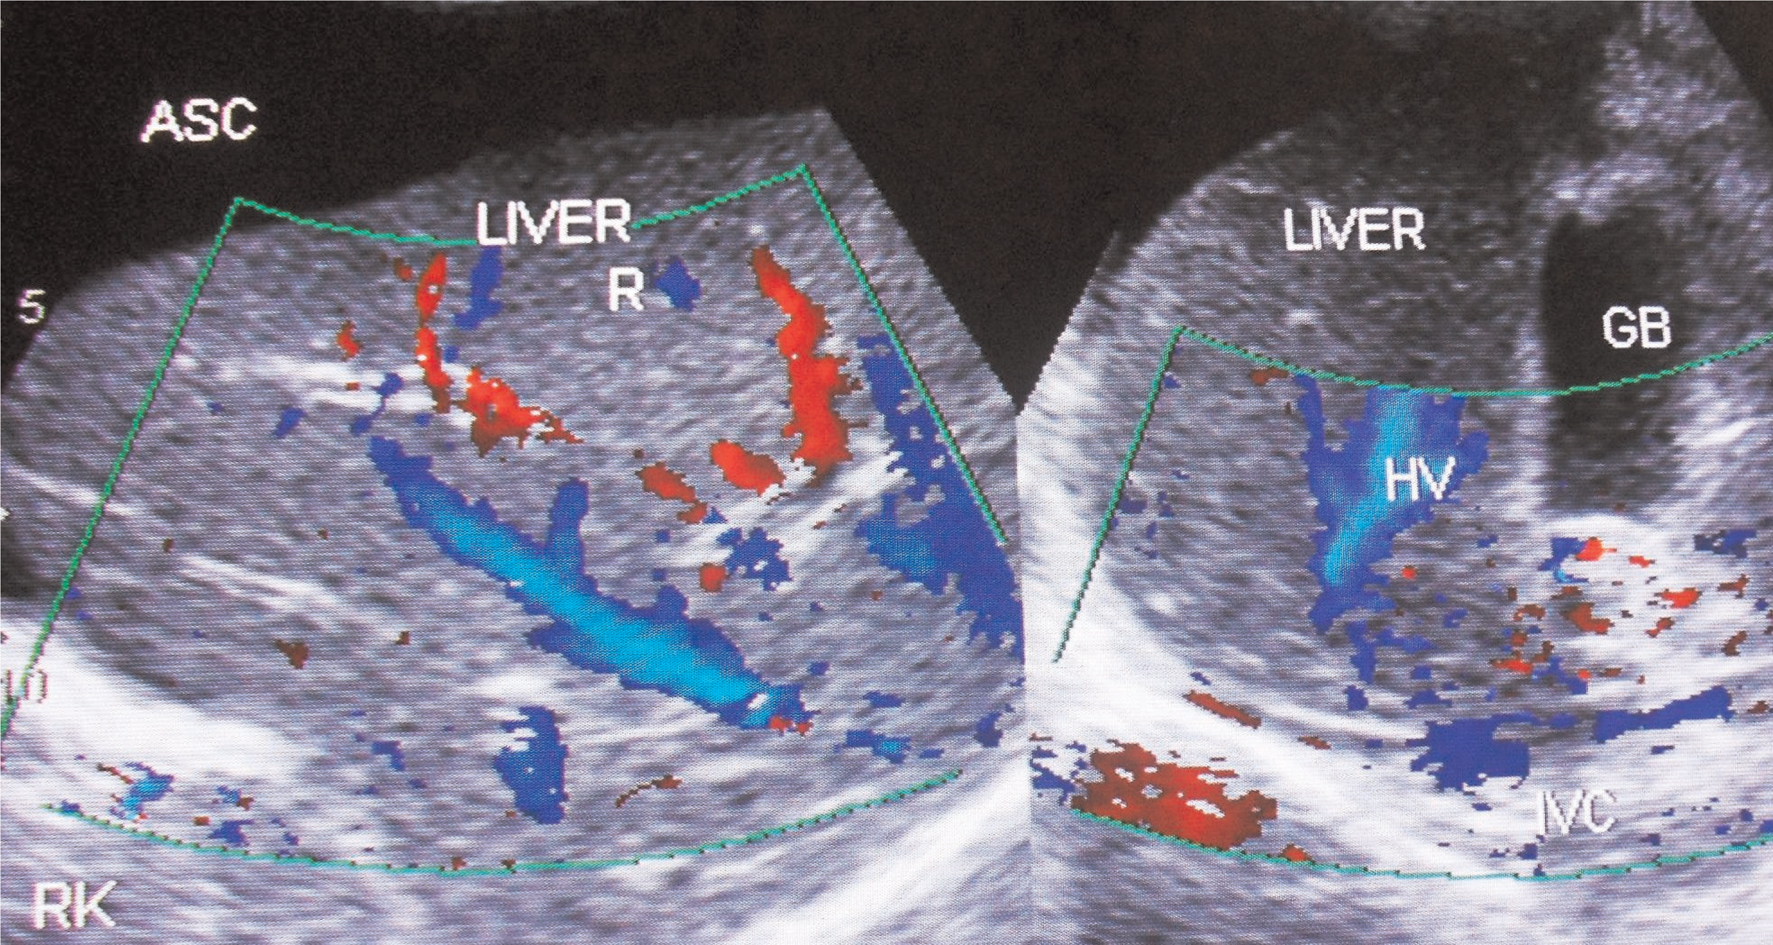

Figure 5. Ultrasonography and color Doppler of a patient with HVCS showing ascites with evidence of chronic peritonitis—Multiple intraperitoneal adhesions. Note the thrombosed, medium-sized branches of portal veins. ASC, ascites. (Copyright: Santosh Man Shrestha).

Fig 6

Figure 6. Ultrasonography and color Doppler of a patient with ascites due to HVCS. IVC shows stenosis at cavo-atrial junction with distal segment dilated. IVC is filled with organized thrombus. There is obstruction to blood flow at the hepatic vein outlets. Note thrombosis of medium-sized tributaries of right hepatic vein. GB, gall bladder; HV, hepatic vein; RHV, right hepatic vein. (Copyright: Santosh Man Shrestha).

HVCS develops in any age group of either sex. Ascites in HVCS is common in persons with poor nutrition or history of alcohol abuse, in whom it is usually precipitated by bacterial infection like puerperal sepsis, chronic diarrhea, and fever or by surgery. Even infants on parenteral nutrition develop this condition. Dilated superficial veins in abdomen with upward blood flow are observed (Figure 4). US/CD examination is diagnostic (75). It shows hepatomegaly and ascites often with evidence of bacterial peritonitis, free-floating particles that settle on standing, acute peritonitis and thick peritoneum with adhesions, loculations, or evidence of perihepatitis indicating chronic peritonitis (Figure 5). Segmental stenosis of medium-sized intra-HVs and prominent main HVs with obstruction to blood flow at the HV outlets will be demonstrated in US/CD. IVC at the site of HV outlet shows stenosis with thick posterior wall with recent and old organized thrombi of different ages along its posterior wall (Figure 6). Gallbladder wall is thick and edematous. Neutrophil leukocytosis or left shift and high level of CRP are common at the onset. Bedside inoculations of blood and ascitic fluid in aerobic blood culture bottle during the initial visit are likely to yield positive culture. Hypersplenism is common in patients with HVCS. Such patients presenting with acute ascites may have normal or slightly elevated WBC count but low platelet count. Levels of serum bilirubin, alanine, and aspartate aminotransferase will be elevated. Cavogram and liver biopsy are not necessary for diagnosis. HVCS patient without ascites usually have normal levels of bilirubin, alanine, and aspartate aminotransferase, but US/CD examination shows IVC with localized stenosis with thick echoic posterior wall in at the level of HV outlet and old organized thrombi along the posterior wall of the distal dilated segment.